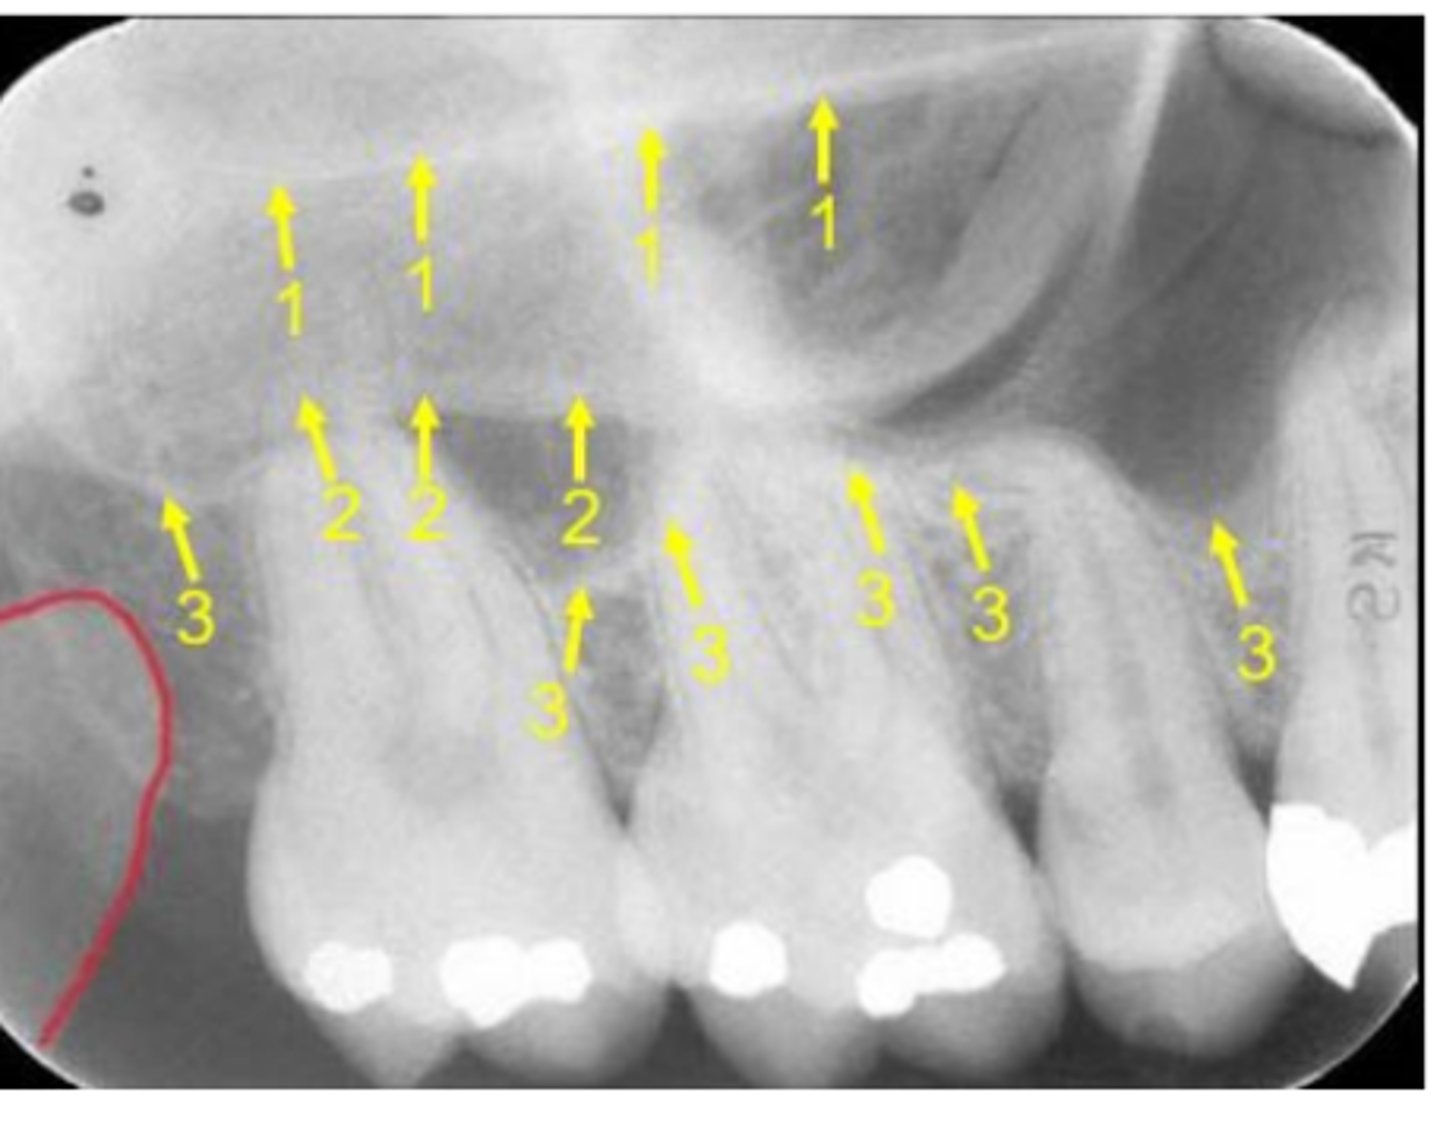

Floor of the maxillary sinus

Name the line indicated by arrows labeled #2.

<p>Name the line indicated by arrows labeled #2.</p>

Zygoma

Name the horizontal radiopaque line labeled #2.

<p>Name the horizontal radiopaque line labeled #2.</p>

Floor of maxillary sinus

Name the curved line scalloping between tooth roots labeled #3.

<p>Name the curved line scalloping between tooth roots labeled #3.</p>

Name the line indicated by arrows labeled #1.

<p>Name the line indicated by arrows labeled #1.</p>

66